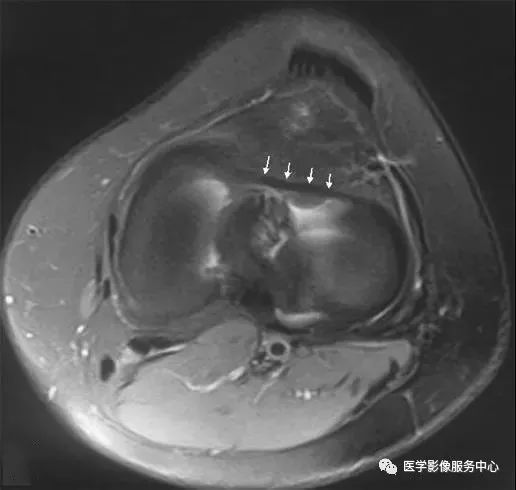

膝外下血管,沿外侧半月板前缘走形,容易将其误认为半月板边缘分离